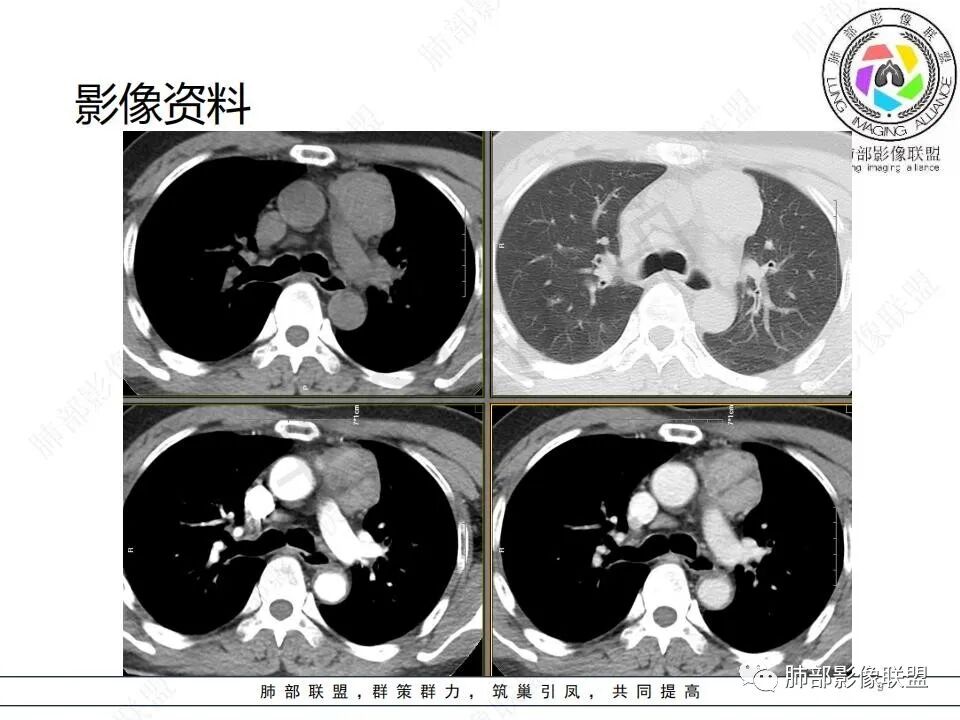

病例资料:

一、赵国干:联盟晨读病例:中年男性,左前纵隔团块状占位,增强呈持续渐进性强化,常规首先考虑胸腺瘤,其次CD、血管瘤(静脉瘤)及副节瘤

二、南边:

病灶定位在前纵隔没问题,类圆形,边界清,有间隔,强化较明显;支持胸腺来源病变,胸腺瘤?类癌?考虑类癌的原因:临床症状、强化

三、谢加平:中老年男性,前纵隔偏左侧肿块,类圆形,无分叶,左侧内乳动脉供血增粗,实性内不均匀强化(具体CT值),有低强化分隔区,肿块内侧边缘毛糙,提示有侵犯特点。有乏力(肌无力)表现,位置来源胸腺瘤(AB?B3型?),与胸腺神经内分泌ca和转移鉴别,Nse抗原、角蛋白19片段和CEA,有不明原因腹痛,可结合腹部CT平扫及增强,排除腹腔内原发肿瘤病变

四、吕军浩:男,56,腹痛、乏力一月,虽然说胸腺瘤可有肌无力变现,纵隔是否责任病灶,难说。就看术后症状能不能改善。影像特点:1、 血管前间隙胸腺区占位,偏一侧,未过中线,在胸腺瘤是良性表现 ;2 、轮廓大致清晰,增强后似见病灶周围渗出样模糊,可能系占位效应,血管淋巴回流受阻引起 ;3 、多个小灶坏死(可以鉴别CD,前无神,所以神经源性肿瘤的AB区不用不用考虑),有低强化分隔;4、 与周围血管间隙还是非常清楚的;5 中度流入型强化 , 综合大概率拍死 AB型胸腺瘤

五、王建国:左前纵隔软组织密度肿块影,边界尚清,密度较均匀,增强扫描渐进性明显强化,其内可见斑片状及线条样低密度影,内乳动脉增粗,考虑胸腺瘤(AB型),鉴别神经内分泌肿瘤,典型类癌

六、白光宇:左前纵膈肿块,边缘光整,明显不均匀渐进强化,其内条片状低密度影,纵膈多发淋巴结,考虑胸腺瘤,胸腺类癌待排

七、冰柠雨露司桂英:前纵隔偏左软组织密度包块,密度较均匀,轮廓规整,与邻近血管结构分界尚清,纵隔未见异常增大淋巴结,增强后中等度强化,内可见低密度分隔,考虑胸腺瘤,AB型?

八、姜文强:晨读病例,中老年,慢性病史。前纵隔占位,纵隔侧和主动脉脂肪间隙清晰,內乳动脉向外推挤,胸膜掀起,轻度强化,内坏死,考虑胸腺瘤

九、宋明亮:男,56岁反复腹疼乏力一个月。前纵隔偏心占位性病变,边缘较清,无明显坏死囊变,似见纤维分隔。考虑胸腺瘤,AB型

十、钟学兰:中年男性,前纵隔偏侧占位,周围血管间隙可见,临床腹痛乏力,增强明显延迟强化,内见低密度纤维分隔,胸腺类癌与胸腺瘤AB型间鉴别